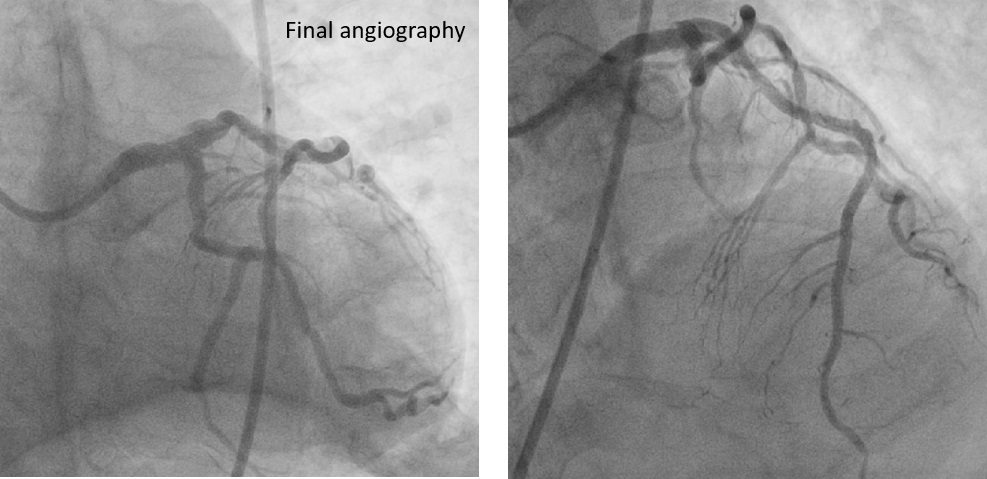

Final angiography showed excellent patency. ECMO was removed uneventfully, and manual hemostasis achieved due to femoral aneurysms precluding device closure.

ECMO-assisted PCI enabled safe revascularization of severe left main and triple-vessel disease with heavy calcification and complex peripheral anatomy. Temporary circulatory support maintained stability during atherectomy and stenting. IVUS confirmed full stent expansion and apposition. Careful planning and coordinated management allowed successful outcome without complications.